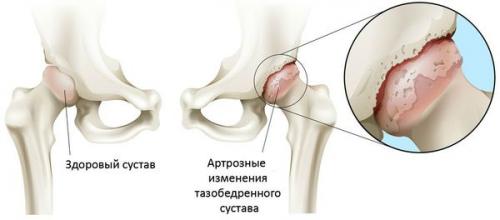

Артроз тазобедренного сустава (коксартроз) — это хроническое дегенеративное заболевание сустава, которое ведёт к деформации костной ткани. При коксартрозе в патологический процесс вовлекаются все компоненты сустава: суставные хрящи, костные структуры, прилегающие к хрящам, синовиальная оболочка, связки, капсула и прилегающие к суставу мышцы. При заболевании разрушается суставной хрящ, появляются микропереломы костей и остеофиты (костные разрастания), возникает воспаление мышечно-связочного аппарата тазобедренного сустава.

При заболевании разрушается суставной хрящ, появляются микропереломы костей и остеофиты (костные разрастания), возникает воспаление мышечно-связочного аппарата тазобедренного сустава.